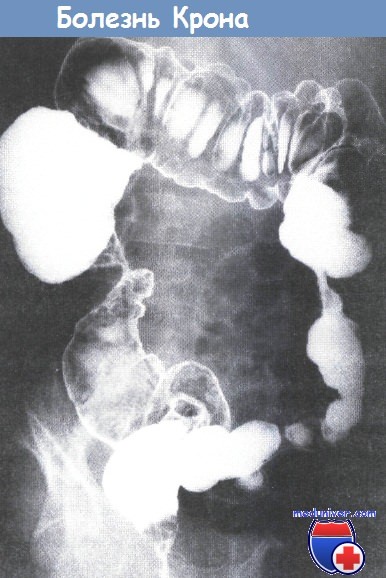

Признаки терминального илеита

Признаки терминального илеита 116 фотографий